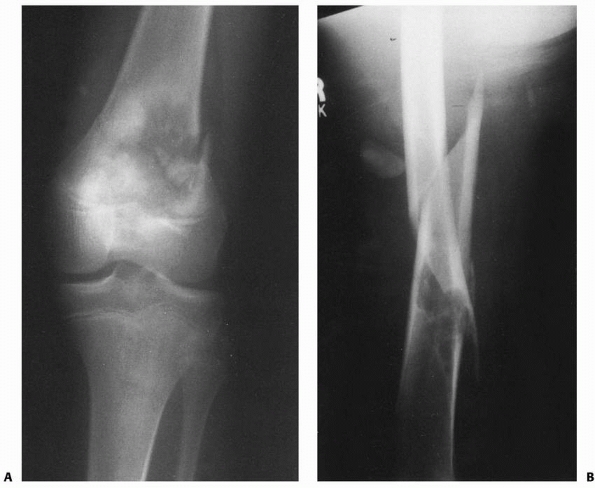

![]() |

FIGURE 22-2 A. Femoral fracture through a poorly demarcated mixed, osteoblastic, osteolytic lesion—an osteosarcoma. B. Sclerotic borders of this lesion in the distal femur are typical of a pathologic fracture through a nonossifying fibroma.